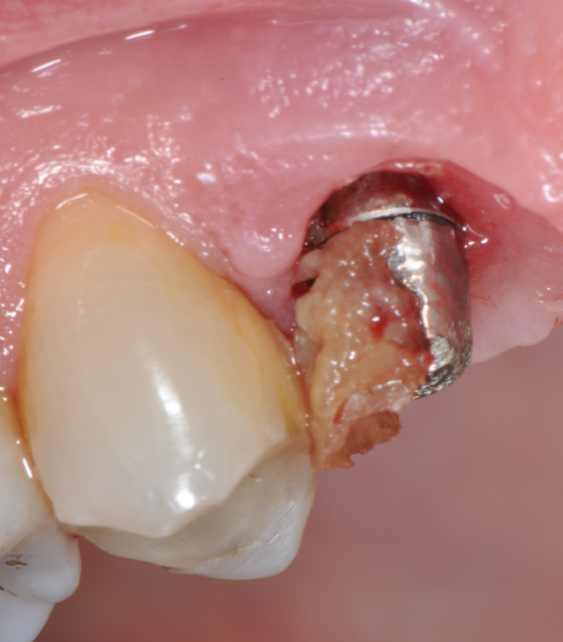

The parameters used to define peri-implant disease usually are: Probing Depth (PD), Crestal Bone Loss (CBL), Bleeding on Probing (BOP) and presence of suppuration and/or fistula.9 Peri-implant mucositis is characterised by soft tissues inflammation witnessed by BOP with or without PD deepening but no effects on the crestal bone while peri-implantitis is characterised by CBL, BOP alone or in conjunction with pus, with or without PD deepening. (Figs. 1, 2 and 3) display the diagnostic steps of a case of peri-implantitis. While mucositis allows a complete healing, peri-implantitis is not reversible.12

Fig.1: Case 1. Peri-implant probing reveals a PPD of 9mm and pus.

Fig.4: Case 1. Clinical appearance after the prosthetic crown removal.